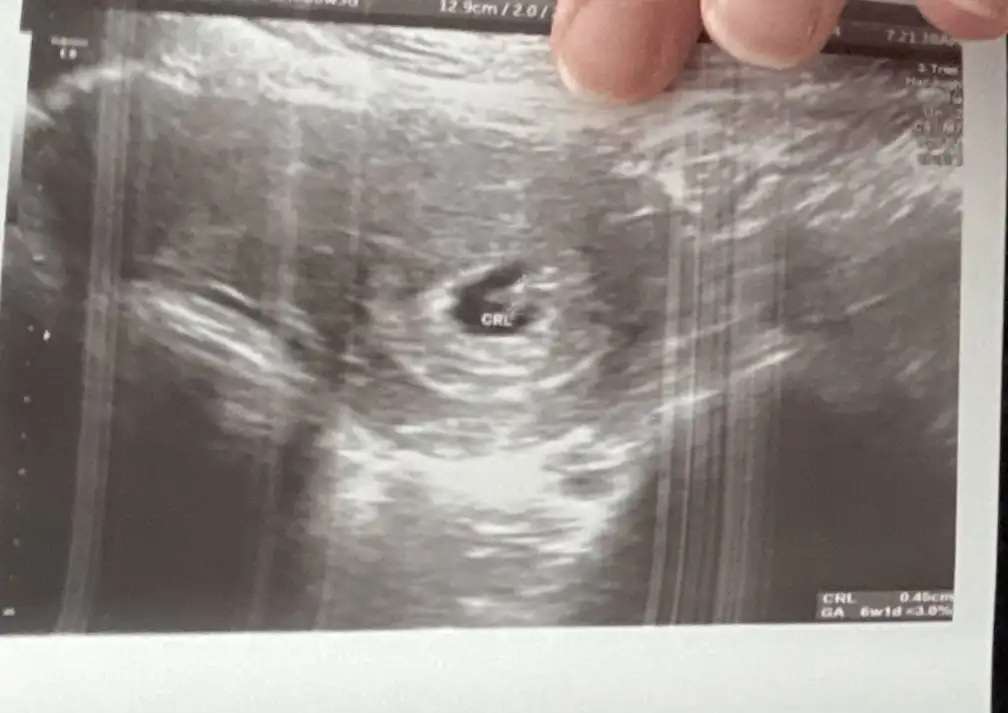

Size zahmet bana da bakabilir misiniz ? İlk resim geniş açılı çekilmiş olan vajinal ultrason 6 haftalık diğer resim karın ultrason 8 haftalık